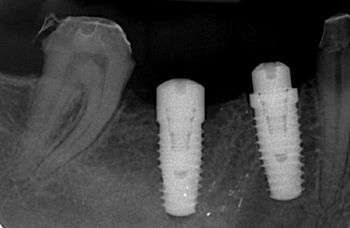

In dentistry, platform switching is a method used to preserve alveolar bone levels around dental implants. The concept refers to placing screwed or friction fit restorative abutments of narrower diameter on implants of wider diameter, rather than placing abutments of similar diameters, referred to as platform matching.

Historically, the diameter of the abutment matched the diameter of the implant platform; for example, a 4.8 mm-wide abutment was placed on a 4.8 mm-wide implant—this can be termed platform-matching.[1]

When platform switching, a narrower abutment diameter for a given implant platform diameter is used; for example, a 4.8 mm-wide implant may be restored with a 3.8 mm-wide or 4.2 mm-wide abutment.[1]